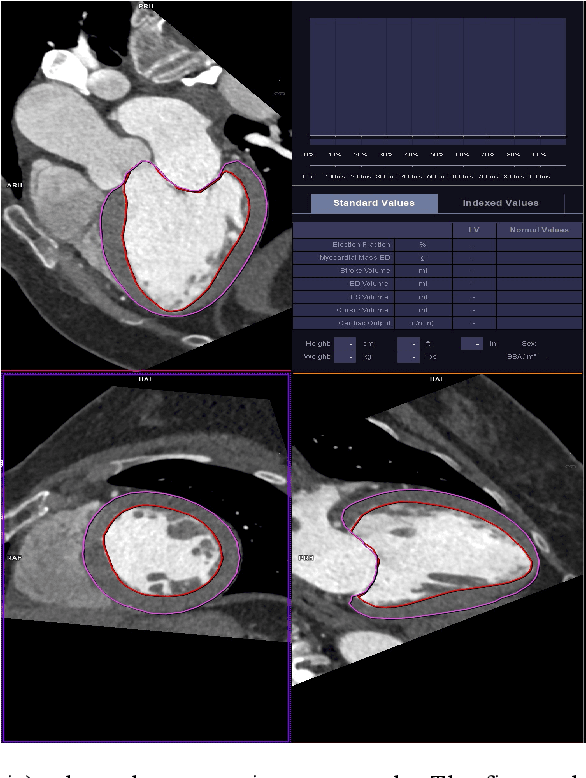

Abstract:The training of deep learning models typically requires extensive data, which are not readily available as large well-curated medical-image datasets for development of artificial intelligence (AI) models applied in Radiology. Recognizing the potential for transfer learning (TL) to allow a fully trained model from one institution to be fine-tuned by another institution using a much small local dataset, this report describes the challenges, methodology, and benefits of TL within the context of developing an AI model for a basic use-case, segmentation of Left Ventricular Myocardium (LVM) on images from 4-dimensional coronary computed tomography angiography. Ultimately, our results from comparisons of LVM segmentation predicted by a model locally trained using random initialization, versus one training-enhanced by TL, showed that a use-case model initiated by TL can be developed with sparse labels with acceptable performance. This process reduces the time required to build a new model in the clinical environment at a different institution.